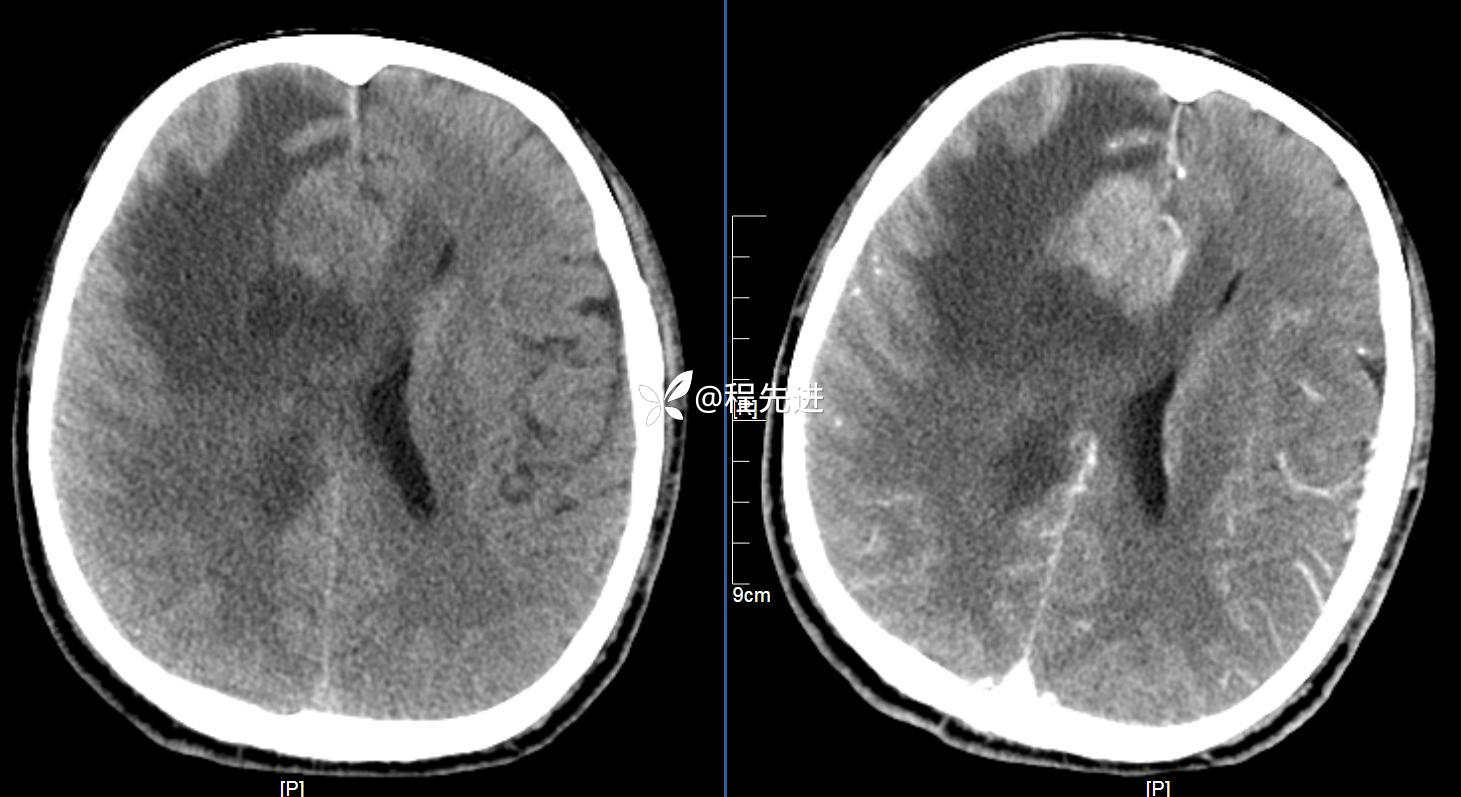

CT平扫+增强: